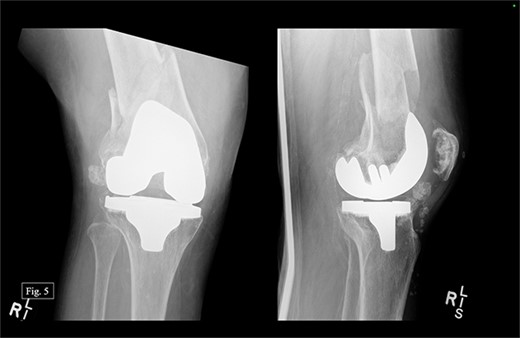

During her most recent visit in February 2024, roughly 4 years after DFR, the patient reported a pain score of 5/10 pain at rest, and bilateral AP, right & left lateral, right & left AP, and full leg-length X-rays were taken. Looking at the APand lateral imaging of the left knee, there were findings of DFR without signs of lucency or subsidence, and the hardware-maintained alignment was intact (Fig. 4). She was able to ambulate with moderate, 6/10 pain and had full passive ROM with similar pain. She was instructed to continue at-home physical therapy and non-steroidal anti-inflammatory drugs (NSAIDs) as needed for pain and to return to the clinic in 6 months for further evaluation.